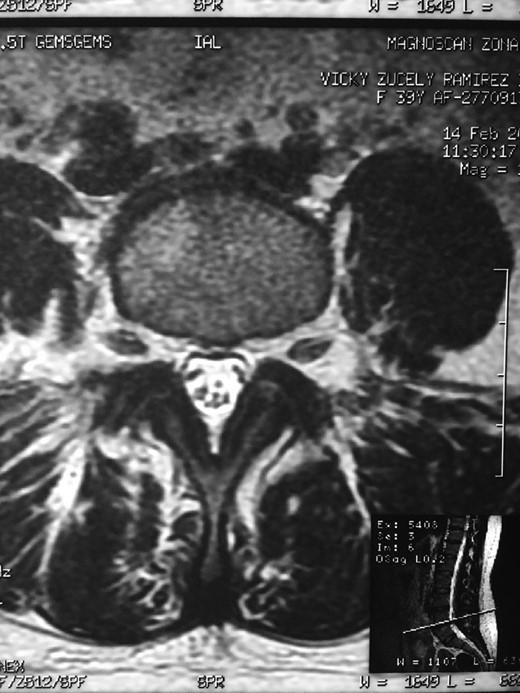

A 42-year-old female presented to the clinic with a history of chronic low back pain. She reported no relevant medical history. She had already been treated in the last 4 years by general practitioners with analgesics and home based physiotherapy with no satisfactory results. She had two previous admissions to the emergency department where morphine was prescribed to control the pain on her lower back. She was under ambulatory treatment with diclofenac, and tizanidine with partial relief of symptoms. Her main complaint was pain on the lower lumbar back with no radiation to the lower extremities. In her physical evaluation she presented limitation to full rotation and bending of the lumbar spine due to pain. Lasegue sign was negative, sensitivity, reflexes, sagittal balance, distal muscular strength and pulses were normal. Radiographs showed an overdeveloped left transverse process of the fifth lumbar vertebra which contacts with the sacrum at the left sacral wing with signs of degeneration at the same site (Fig. 1). Magnetic resonance imaging (MRI) studies were obtained (Figs 2–5). The patient was taken to the operating room where infiltration with 1 mL of lidocaine and 40 mg of Triamcinolone was performed in the pseudoarticulation between the left transverse process and the sacrum under fluoroscopic guidance. She reported a complete relief of pain after the procedure. At three months follow-up she was managed with strengthening and stabilizing exercises for the lumbar spine and postural education was initiated. She remains asymptomatic at her 12 months follow up.

RMN of the patient showing smaller facets in the anomalous articulation and healthy disc compared to the supradjacent one (next figure).

Degenerative changes at the facets and disc in the adjacent segment.

The partial fusion at the lower part of the lumbosacral transition produces important alterations in normal biomechanics at the levels immediately above and below the LSTV. Changes such as hypermobility and abnormal torque moments are present at the level above the LSTV, predisposing it to early degeneration (early disc pathology and facet joint degenerative disease). Restricted movement below the LSTV produces a protective effect against degeneration of disc and facets and is related to changes (facets are smaller and coronally oriented) in the dimensions of the lower level facet joints [7]. These alterations can be verified in the adjacent levels of the LSTV in our patient.